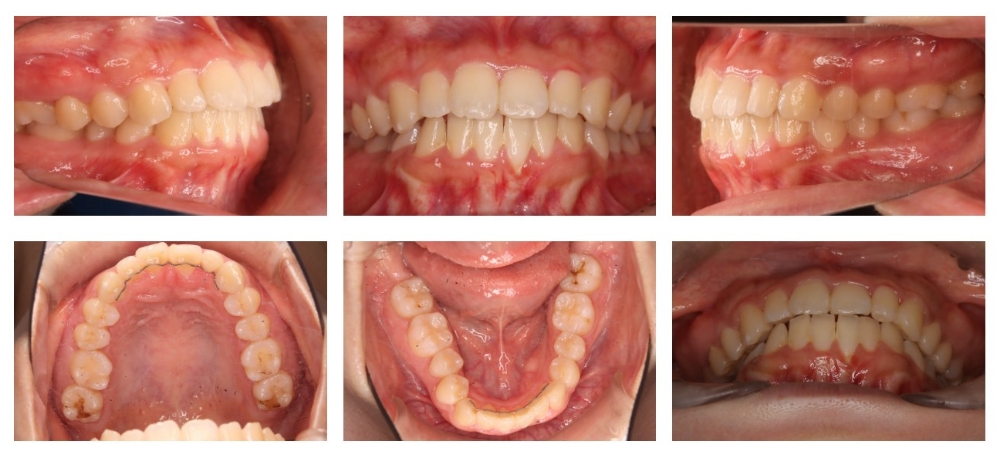

治療前

叢生 交叉咬合(Cross bite) 前歯 シザースバイト

主訴 横顔(口元が出ている), 笑った時の歯茎の見え方

年齢/性別 10代 / 女性

抜歯部位 非抜歯

使用装置 アライナー(インビザライン)

治療期間 5年4ヶ月

リテーナー 上LBR, 下LBR, 上クリアリテーナー, 下クリアリテーナー